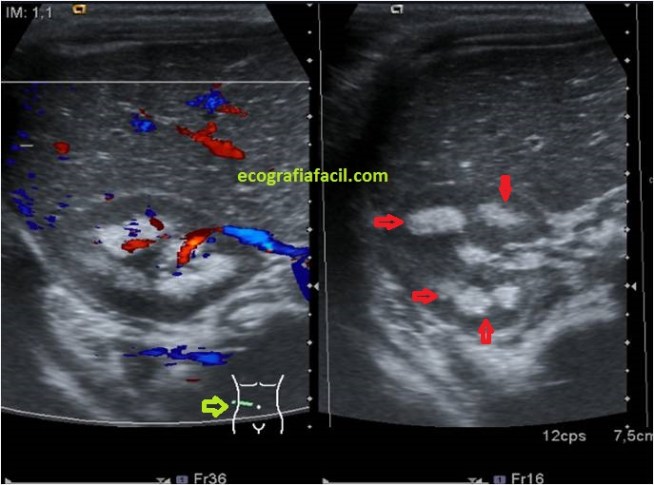

Vamos a ver unos riñones así en la ecografía:

En las imágenes superiores ves un corte longitudinal y otro axial del riñón.Marcado con círculos o flechas rojas, los pielones caliciales hiperecogénicos, muy llamativamente, indican patología a dicho nivel, la corteza renal, hipoecogénica y normal.

In the upper images you see a longitudinal and axial cut of the kidney. Marked with red circles or arrows, the hyperechoic calyceal skin, very strikingly, indicates pathology at this level, the renal cortex, hypoechoic and normal.